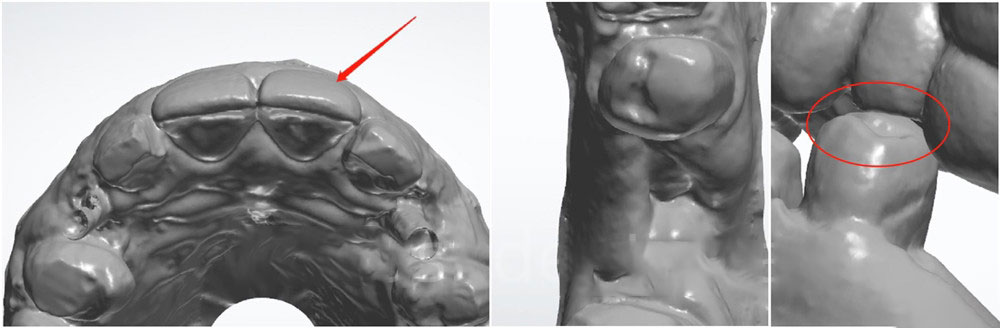

1. Prepare teeth before sending dental cases to us

Please always prepare teeth before oral scanning or taking impressions (unless you need non-prep veneers or diagnostic wax-up). Please do not ask us to prepare teeth in our lab, because you could have difficult chairside adjustments and have problems with fitting.

Teeth without preparation